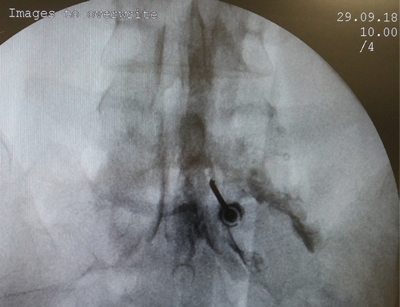

Material y métodos: Se realizó un estudio prospectivo sobre 52 pacientes con lumbociatálgia crónica unilateral, a los que se le realizó una inyección epidural lumbar de esteroides. En 39 de ellos se valoró en condiciones basales y al mes del procedimiento, el dolor y el catastrofismo mediante el Inventario Abreviado de Dolor y la Escala de Catastrofismo. Se definó como “respondedores” a los pacientes con disminución de 2 puntos o más en la intensidad del dolor. Para el catastrofismo se consideró un score de 30 como severo. Un valor de p < 0,05 se consideró de significancia estadística.

Material an methods: A prospective study was conducted on 52 patients with unilateral lumbosacral radicular pain. In 39 of them, the Brief Pain Inventory and the Catastrophism Scale was applied before and one month afer a epidural steroid injection. Responderes to treatment ere defined with a decrease of 2 points or more in pain intensity. For catastrophism, a score of 30 was considered severe. A value of p < 0.05 was taken as statistical significance.